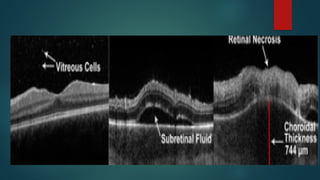

Posterior segment features

1. Retinitis and Vasculitis

 Initially there is a solitary white lesion with granular borders

 Associated with vasculitis which eventually causes FLAME shaped

hemorrhages (PIZZA PIE appearance)

 Macular involvement causes vision loss

 Initially unilateral, but later progresses to become a bilateral disease

 INDOLENT FORM : peripheral granular opacities with occasional

hemorrhage

 FULMINANT FORM : Vast areas of necrosis with prominent hemorrhages

along with areas of progressive retinal atrophy

4. Retinal necrosis : When active

inflammation settles down areas with

irregular pigmentation, atrophy and

holes are seen.

This can lead to RRD